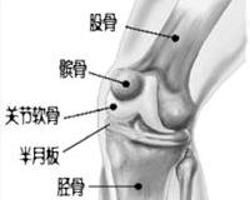

膝關節骨性關節炎是指由於膝關節軟骨變性、骨質增生而引起的一種慢性骨關節疾患,主要表現是關節疼痛和活動不靈活,X線表現關節間隙變窄,軟骨下骨質緻密,骨小梁斷裂,有硬化和囊性變。又稱為膝關節增生性關節炎、退行性關節炎及骨性關節病等。本病多發生於中老年人,也可發生於青年人,可單側發病,也可雙側發病。

5.膝關節正、側位X照片,顯示髕骨、股骨髁、脛骨平台關節緣呈唇樣骨質增生,脛骨髁間隆突變尖,關節間隙變窄,軟骨下骨質緻密,有時可見關節內游離體。